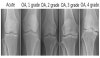

2. 방사선학적 분류 : Kellgren-Lawrence grade

X-ray : Kellgren-Lawrence grade